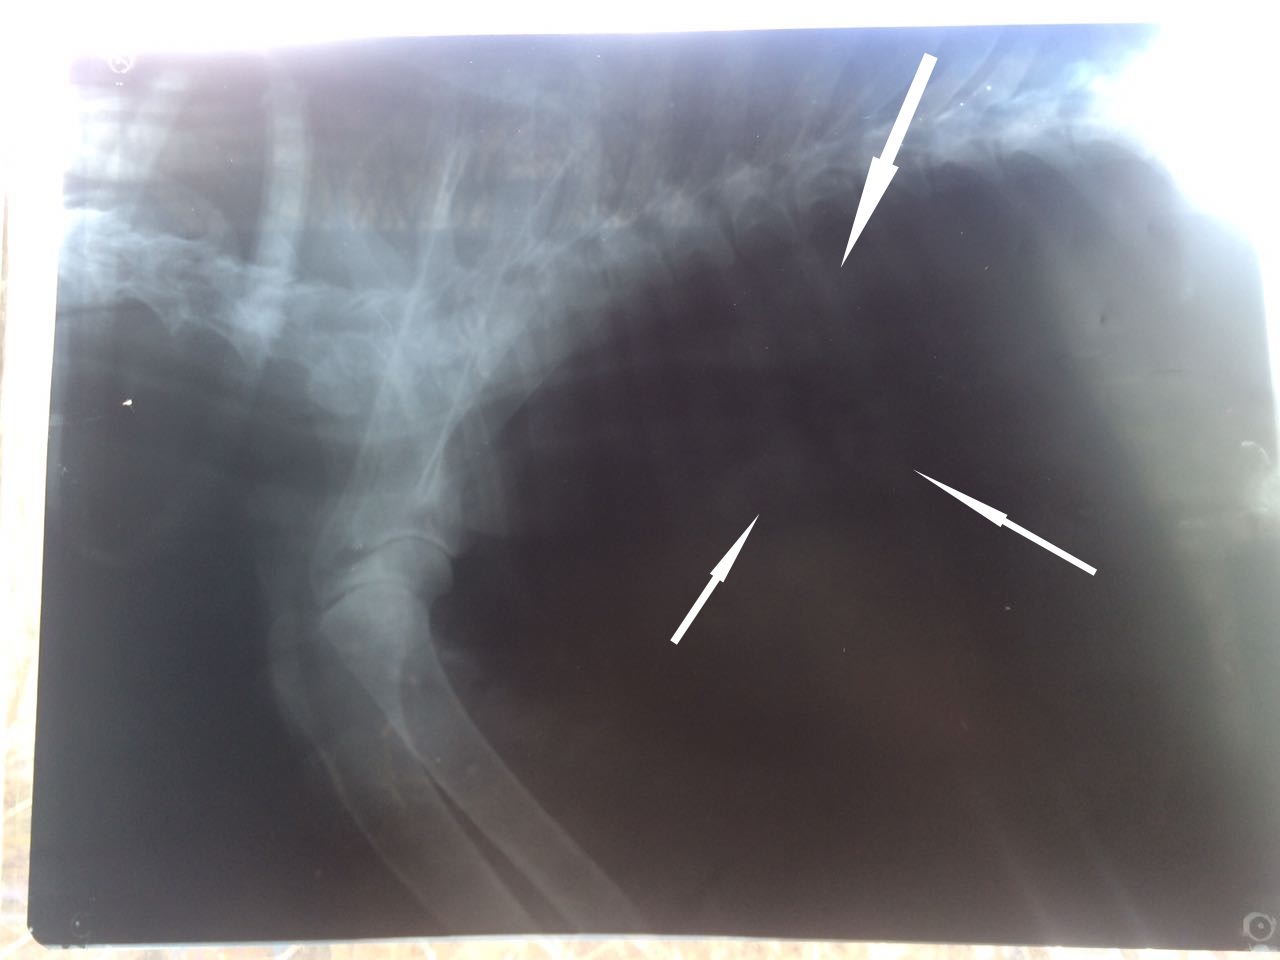

Легкие чистые на рентгене,но не совсем понятная история с образованием между вокруг пищевода и возможно это давит на трахею.На снимке отметила стрелочками.Что то наверняка,слизь или возможно еще что-то рентген не может рассказать окончательно.Во всяком случае в этом качестве.Конечно я бы сделала ей цифровой,но пока такой возможности нет.А МРТ уж слишком дорогое удовольствие и наркоз.

Кать, ничего не смогла разобрать на рентгене. Надо его повторить, до решения операции и сравнить.